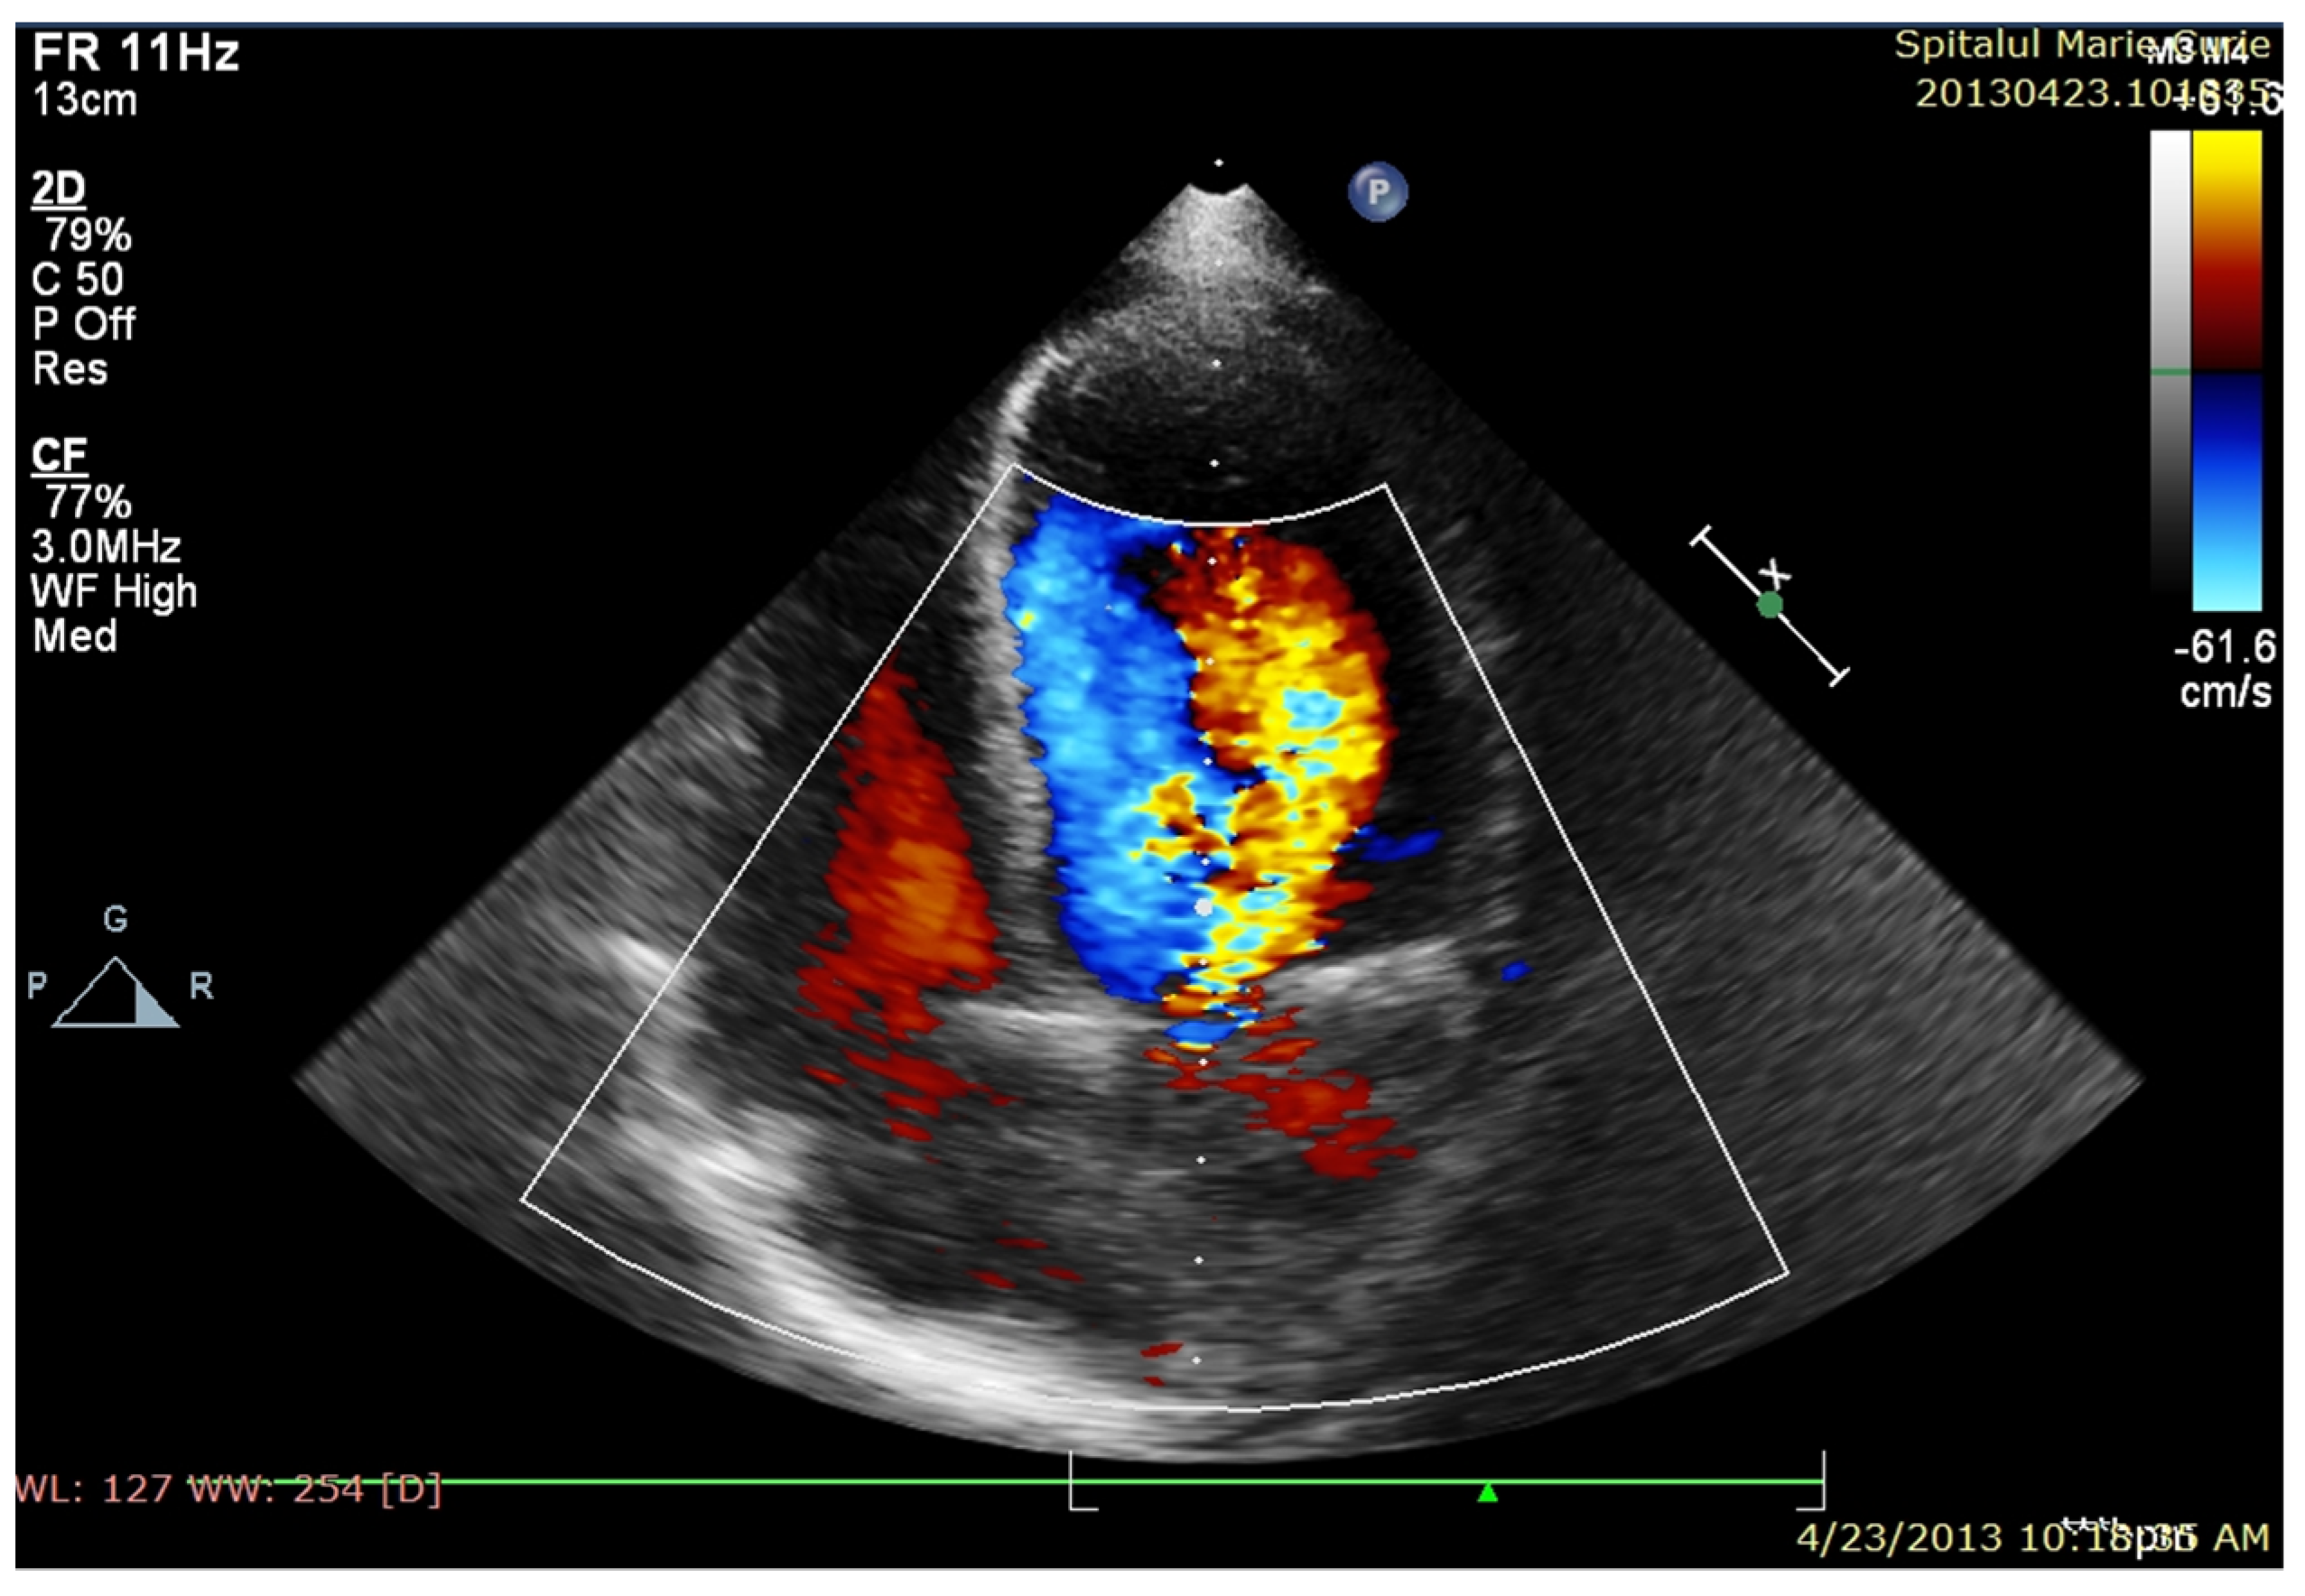

After four days of admission, vesper fever (38.2 C) progressively recurred, and the biological inflammatory syndrome slowly developed. Management was changed to Meropenem at 100 mg/kg/day and Linezolid at 25 mg/kg/day (Vancomycin was replaced with Linezolid due to a severe allergic reaction after the second administration), and this was continued for six weeks. In the first week of treatment, the patient started to develop a significant new diastolic murmur, and echocardiography confirmed spontaneous drainage of the perivalvular aortic abscess, resulting in severe aortic insufficiency and dilation of the left aortic coronary sinus (Figure 1a,b), along with a decrease in LVEF (45%).

Figure 1. (a) TTE PLAX—paravalvular aortic abscess—in the course of formation; (b) after spontaneous evacuation.